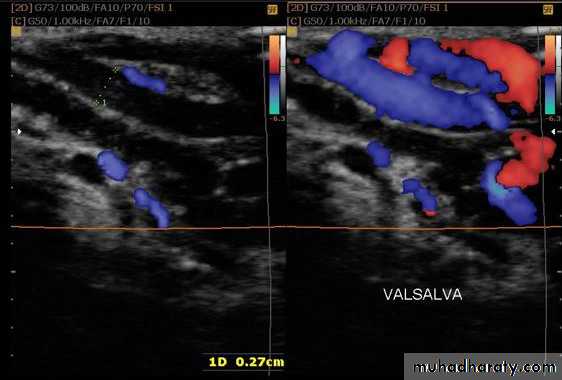

Doppler study of scrotal Swelling